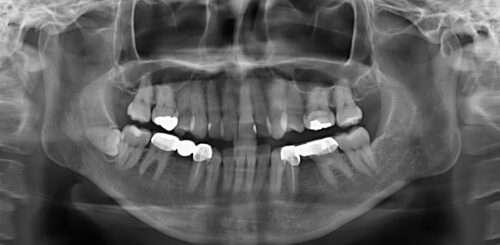

初診時のパノラマエックス線写真